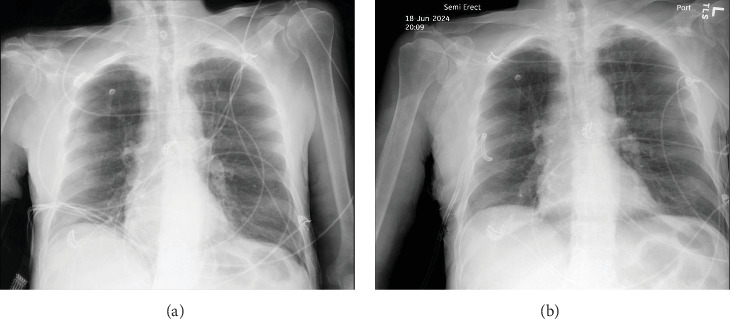

Peptic ulcer disease (PUD) results from erosion and ulceration of the upper digestive tract mucosa. Clinical presentations can vary from asymptomatic to severe complications such as perforation, strictures, or bleeding. Perforation can release enteric contents and gas into the abdomen, leading to intra-abdominal sepsis, requiring surgical intervention for source control and repair. We present a case of a 69-year-old male who developed both Fournier's gangrene and a right-sided pneumothorax secondary to a nontraumatic perforated duodenal ulcer. The patient underwent an emergent thoracostomy, laparotomy with Graham omentoplasty, and extensive debridement with successful outcome. While rare complications like pneumothorax and necrotizing soft tissue infections have been documented, their simultaneous occurrence from a nontraumatic ulcer perforation is unprecedented in literature. Previous reports suggest enteric contents can traverse retroperitoneal fascial planes and peritoneal defects to reach distant anatomical sites as a possible mechanism for these complications. This case highlights the potential for atypical presentations of PUD and the importance of comprehensive evaluation, early recognition, and prompt surgical intervention.